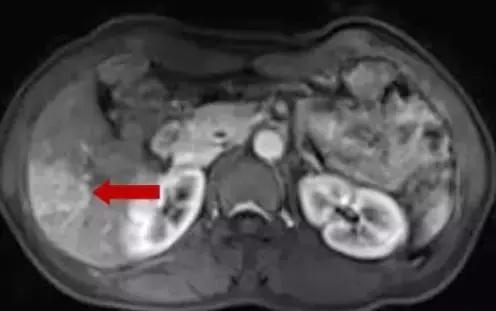

术前MDT讨论,拟行超声引导下肝转移瘤射频消融术+腹腔镜下右半结肠癌根治术。在超声引导下肝转移射频消融术前讨论,考虑肝内转移病灶临近肝包膜下,病灶边缘可见肝右静脉及其分支环绕,拟行双针多点重叠消融,术中遵循消融范围至少≥癌周1cm,先深后浅原则,先沿肝静脉布针,两针间距不超过2cm。